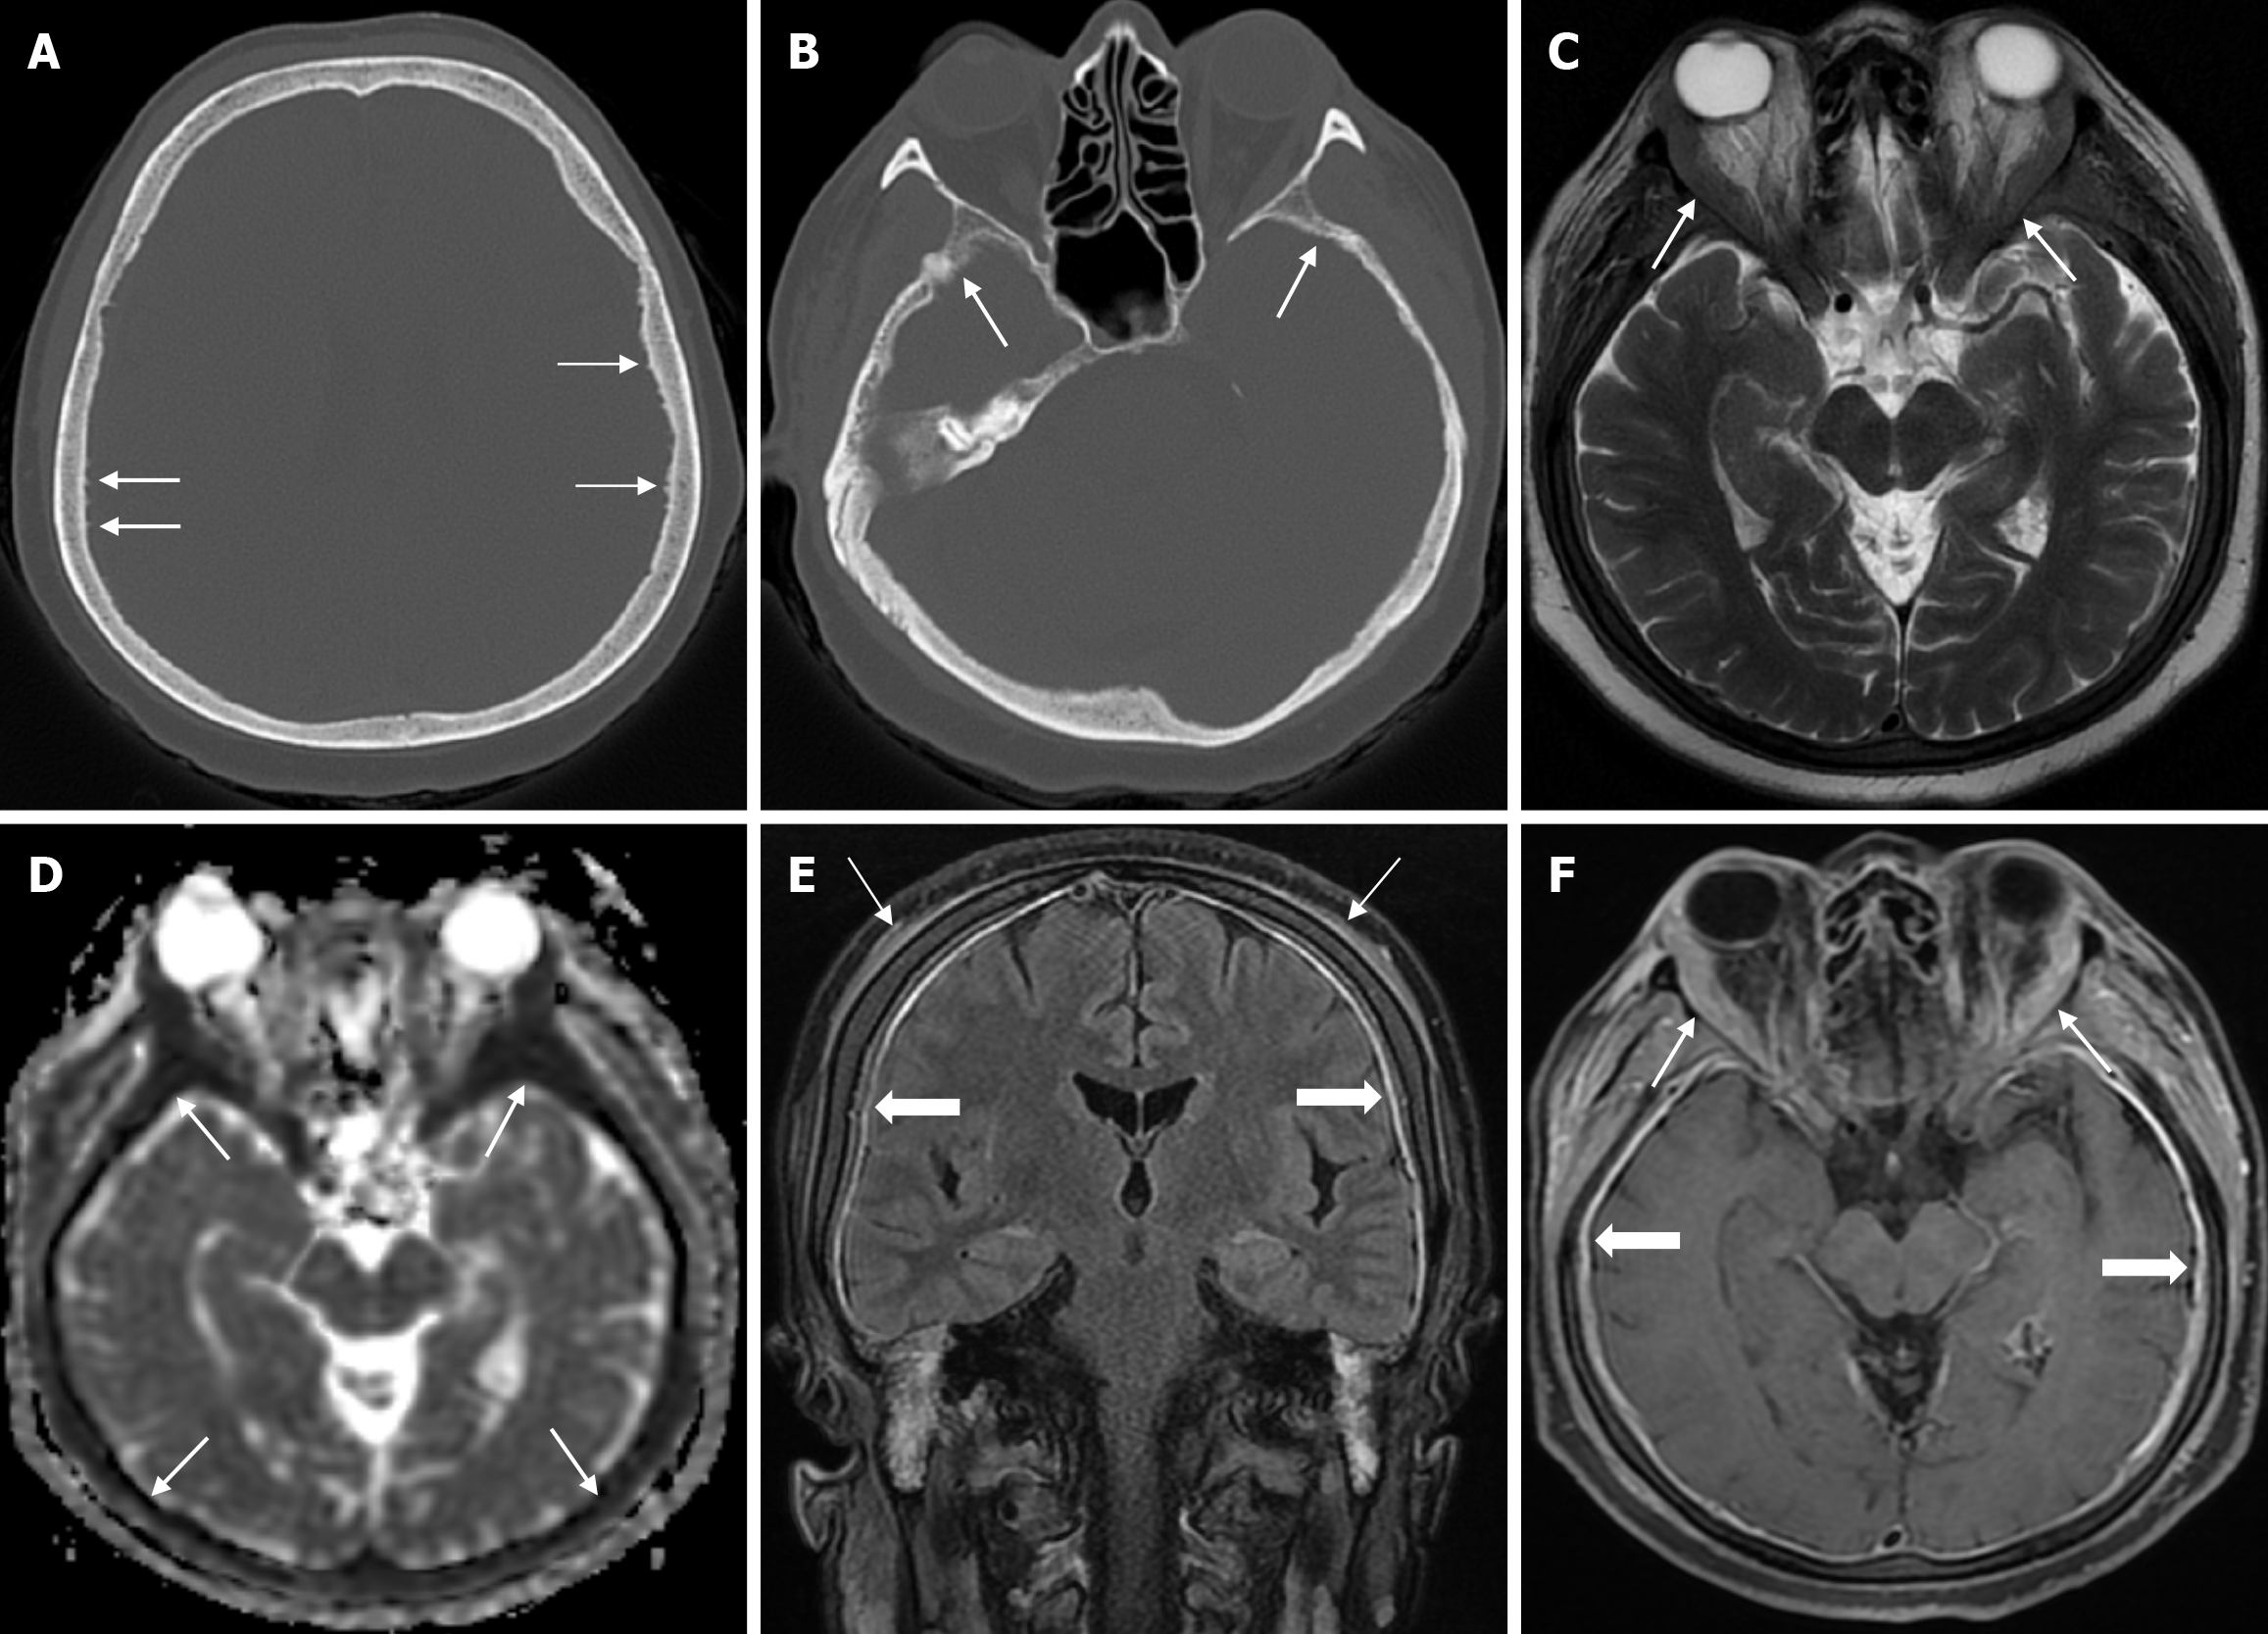

Arachnoid granulations (Pacchionian granulations) are cerebrospinal fluid-filled projections that extend from the subarachnoid space through openings in the dura into the venous sinuses and can be seen macroscopically. Their incidence varies from 0.3% to 55%. Arachnoid granulations are usually seen in millimeter dimensions, but may grow to fill the dural sinuses or arch the inner table[11]. In addition, intraosseous arachnoid granulations can sometimes extend to the inner table of the bone, causing scalloping, remodeling or bone erosion of the inner table[12]. The prevalence of arachnoid granulations increases with age, but there is no difference in gender distribution. Arachnoid granulations with a slight left hemispheric predominance are found in the dural venous sinuses, most frequently in the transverse sinuses and especially in the middle or lateral parts. The second most common location is the superior sagittal sinus, but they can be found anywhere in the dural venous sinuses. Arachnoid granulations are usually detected incidentally. If they fill and expand the dural sinuses, causing partial sinus obstruction, they may cause symptoms of increased intracranial pressure due to venous hypertension. They are usually associated with headaches. Arachnoid granulations may be seen as radiolucent areas on plain radiography of the skull or may cause compression on the inner table of the skull. On CT imaging, arachnoid granulations can be seen as sharply demarcated, hypodense structures in close relation to the dural venous sinus. On MRI, they usually show hyperintense signal on T2-weighted images and hypointense or isointense signal on T1-weighted images compared to brain parenchyma (Figure 1). On CT angiography, MR angiography or catheter angiography imaging, arachnoid granulations appear as oval or round filling defects in the dural venous sinuses during the venous phase[11]. Recent advances in radiology have made it possible to identify brain herniations into the arachnoid granulation by improving image quality with higher resolution and thinner slice three-dimensional T1-weighted and T2-weighted MRI sequences (Figure 2). Brain herniation into the arachnoid granulation is rare in the literature, and the incidence of brain herniation into the calvarial or dural sinuses has been reported to be 0.32%[13]. Arachnoid granulations may be confused with pathological processes in the dural venous sinuses[11]. In the differential diagnosis of arachnoid granulations, venous sinus thrombosis, dural-based tumors, or structures such as septa and fat that may cause filling defects in the dural venous sinuses should be considered[12]. Dural sinus thrombosis usually fills an entire sinus segment or several sinuses and may extend to the cortical veins, whereas arachnoid granulations appear as focal and well-defined defects. Fresh thrombus in the dural sinuses are hyperdense on CT and hyperintense on T1-weighted MRI. Differential tumor diagnosis can be made based on its shape, lack of contrast enhancement and diffusion restriction[11].

The transcalvarial venous channels are the openings in the calvarium that connect the dural venous sinuses to the extracranial veins via emissary veins. They are usually seen as serpentine or linear lucencies with sclerotic margins along the skull, and when these vessels are dilated they are known as venous lakes. Venous lakes are sometimes confused with fractures or sutures[14]. Venous lakes are present in about 15% of patients and are not associated with age or gender[15]. Venous lakes appear on CT as round or oval lucencies at the level of the skull base (Figure 3). On MRI, they show medium or low signal intensity on T1-weighted images, high signal on T2-weighted images, and significant contrast enhancement is seen in contrast-enhanced series[14]. It is important to distinguish venous structures from metastases. Metastases often show restricted diffusion within the lesion due to high cellularity. In addition, metastases may show increased blood flow within the lesion. Metastases often invade adjacent tissues[15].

Epidermoid cysts are small or medium-sized, benign, and slow-growing tumors that arise from the remnants of ectodermal cells in the bones of the skull. These cysts can also develop after trauma or surgery. Epidermoid cysts are lined with squamous epithelium. They contain deposits of cholesterol and keratin. These cysts constitute less than 1% of primary intracranial tumours, while intradiploic epidermoid cysts account for less than 0.25% of intracranial tumours. These tumors can occur at any age from the first decade of life to the seventh decade, with a mean age of 32-38 years, and there is no gender predilection. Epidermoid cysts are most commonly found in the frontal, parietal and occipital regions and often involve more than one bone. Epidermoid cysts appear on plain radiography as round or lobulated lytic areas with smooth and sclerotic margins. On CT they appear as non-contrast enhanced intradiploic lytic hypodense lesions with smooth sclerotic borders. Epidermoid cysts often cause remodeling and widening of the inner and outer tables. Epidermoid cysts that appear hyperdense on CT due to bleeding, calcification or high protein content are called white epidermoids and are observed quite rarely. On MRI, epidermoid cysts appear isointense/hyperintense on T2-weighted and fluid-attenuated inversion recovery (FLAIR) images and slightly hyperintense on T1-weighted images (Figure 4). These lesions restrict diffusion on diffusion-weighted imaging but show no contrast enhancement on contrast enhanced sequences[19].

The beaten copper skull shows prominent convolutional markings on several bones of the skull. These convolutional markings normally appear between the ages of 2-3 and 5-7 years, which are periods of rapid brain growth. The occurrence of convolutional markings in children younger than 18 months should suggest a cause leading to increased intracranial pressure due to processes such as obstructive hydrocephalus, craniosynostosis or intracranial masses. Beaten copper skull pattern develops because of pressure applied to the soft skull by the growing brain. The beaten copper skull is usually confined to the posterior part of the inner table of the skull, but this appearance can affect the entire skull. Plain radiography of the skull can be an important diagnostic tool to detect increased intracranial pressure. In children, CT and three-dimensional reconstructions are best used to evaluate the convolutional markings (Figure 5) and cerebral ridges for surgical planning[23].

Atretic encephalocele is a midline scalp mass covered by skin containing meninges and neural remnants and/or degenerated brain tissue. In atretic encephaloceles, the brain tissue in the scalp degenerates and may remain attached to the dura mater by a fibrous stalk intracranially. Atretic cephaloceles may be associated with a persistent falcine vein characterized by a vertical embryonic position of the straight sinüs (Figure 6). Most atretic encephaloceles are parietal in location. On CT imaging, a subgaleal soft tissue mass may be seen in a “spinning top” configuration. CT imaging helps visualize bone defects, while MRI helps determine the contents of the encephalocele[3]. The lesions most commonly confused with atretic encephaloceles are sinus pericranii and dermoid cysts[25].

Sinus pericranii is a rare vascular anomaly with transosseous venous channels connecting the intracranial venous system to the extracranial veins[26]. It is usually congenital, but trauma is thought to be a predisposing factor. The congenital lesion has an endothelial lining, while the acquired lesion has a connective tissue lining. The male to female ratio is 2/1 and the condition can be seen in all age groups, but is usually diagnosed before the age of 30. Sinus pericranii is most commonly located near the midline. The frontal region is most commonly involved, followed by the parietal and occipital regions, while lateral localization is rare[27]. Sinus pericranii is often associated with other intracranial venous anomalies, such as developmental venous anomalies or venous vascular malformations. Affected patients typically present with a soft cutaneous mass that expands in the supine position or during the Valsalva manoeuvre and contracts on standing. Patients are usually asymptomatic, but headache, dizziness or nausea may occasionally occur. Sinus pericranii is classified as dominant (the majority of venous flow communicates with the sinus pericranii) or accessory (only a portion of intracranial venous flow communicates with the sinus pericranii). CT venography shows a calvarial defect and anomalous communication between the dural venous sinus and the extracranial veins (Figure 7). Thrombosis of the dominant sinus pericranii, where most intracranial venous drainage occurs, is associated with life-threatening complications such as venous congestion and/or infarction. Treatment is contraindicated in the dominant type. For accessory sinus pericranii, interventional (i.e. surgical or endovascular) treatment may be indicated to improve symptoms, prevent future traumatic haemorrhage and air embolism, and for cosmetic reasons[26]. Sinus pericranii should be suspected when a soft, fluctuant mass is detected near the intracranial sinus and can vary in size. MRI shows the relationship of the lesion to the underlying sinus, while direct injection of contrast medium through the wall of the mass shows rapid passage of contrast into the sinus[27]. Also, MRI shows variable signal intensity due to flow artefacts[26].

The prevalence of cranial osteomyelitis is 1.5% of all osteomyelitis cases, with a mortality rate of 20%-40%[45]. In developed countries, postoperative craniotomy infections are the most common cause of osteomyelitis, whereas in developing countries, sinusitis and scalp infections are the most common causes. It may occur as a complication of hematogenous spread or trauma. CT findings in the acute phase of osteomyelitis include areas of rarefaction and loss of diploic bone trabeculae; demineralization, erosion or thinning of the cortical bone table; and extracranial and subperiosteal abscesses. Diploic bone sclerosis and cortical bone thickening, radiolucent areas, and cortical disruption may occur in the chronic phase. Sequestration occurs as a result of the destruction of the skull base. On MRI may reveal an intracranial extension, particularly an epidural abscess and/or a subdural empyema. MRI findings in the acute phase of osteomyelitis include inflammatory replacement of diploic bone fat, widening of the diploic space, thinning of the skull base, increased signal intensity on T2-weighted images and contrast enhancement on T1-weighted images (Figure 12). In the chronic phase, sequestration, contrast enhancement in soft tissues and dura, and destruction of cortical bone fragments are seen. Bone scans using technetium-99m, gallium-67 citrate, single-photon emission computed tomography (SPECT), PET or PET-CT scans with 18F-fluorodeoxyglucose are highly effective in detecting cranial bone infections[46].